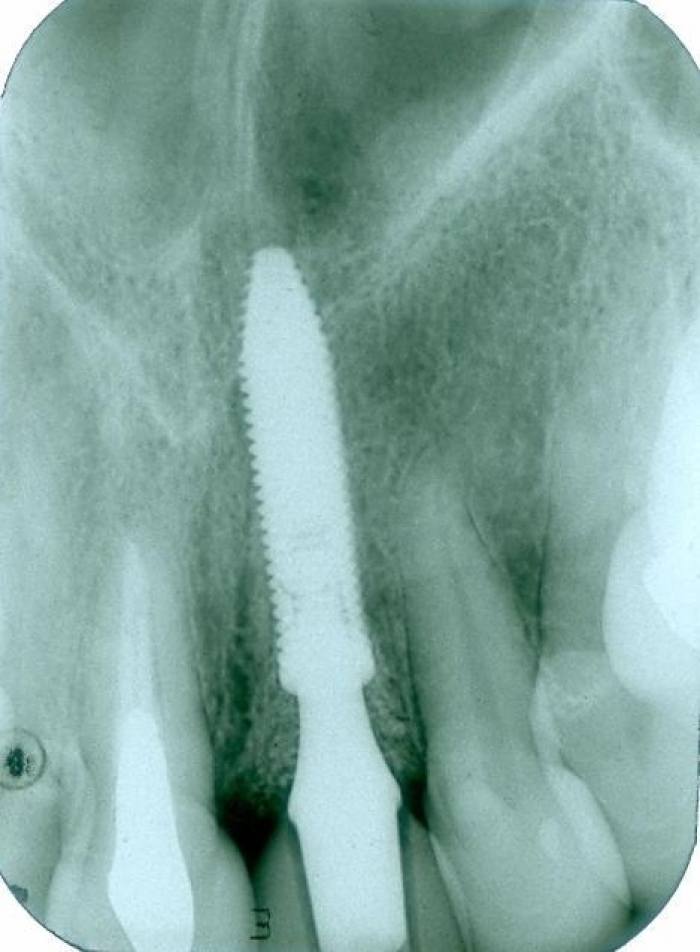

Raio X com prótese provisória fixa sobre o implante